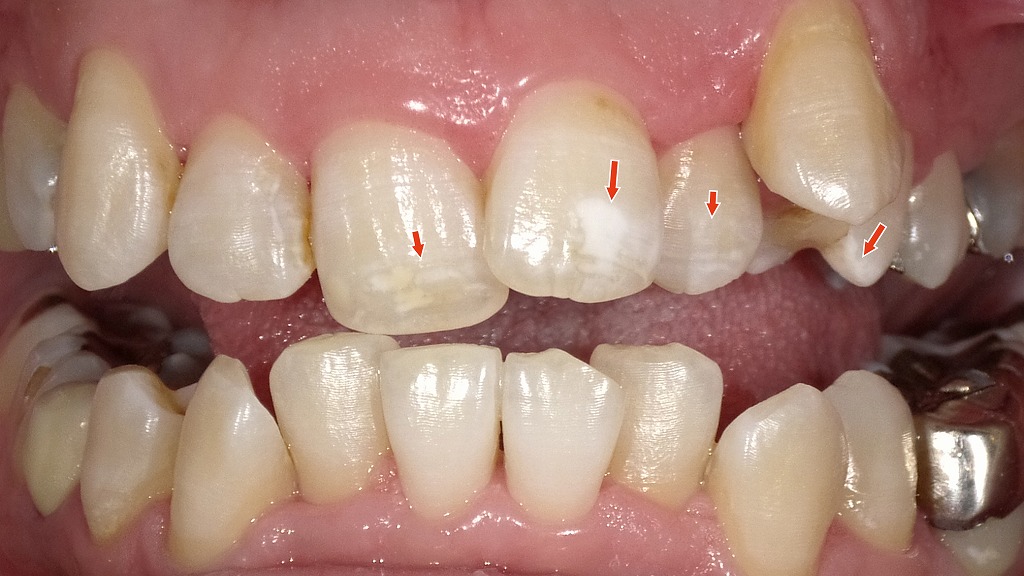

1枚目の画像:術前

1枚目の画像では、上顎前歯(特に中央の2本)に白く不透明な部分が見られます。これはエナメル質形成不全によるホワイトスポットです。歯が作られる発育期に、エナメル質のミネラルが十分に沈着せず、部分的に構造が弱くなった結果、光の反射が異なり白く濁って見える状態です。むし歯ではなく、表面は滑らかで痛みもありませんが、審美的に気になる方が多い症状です。